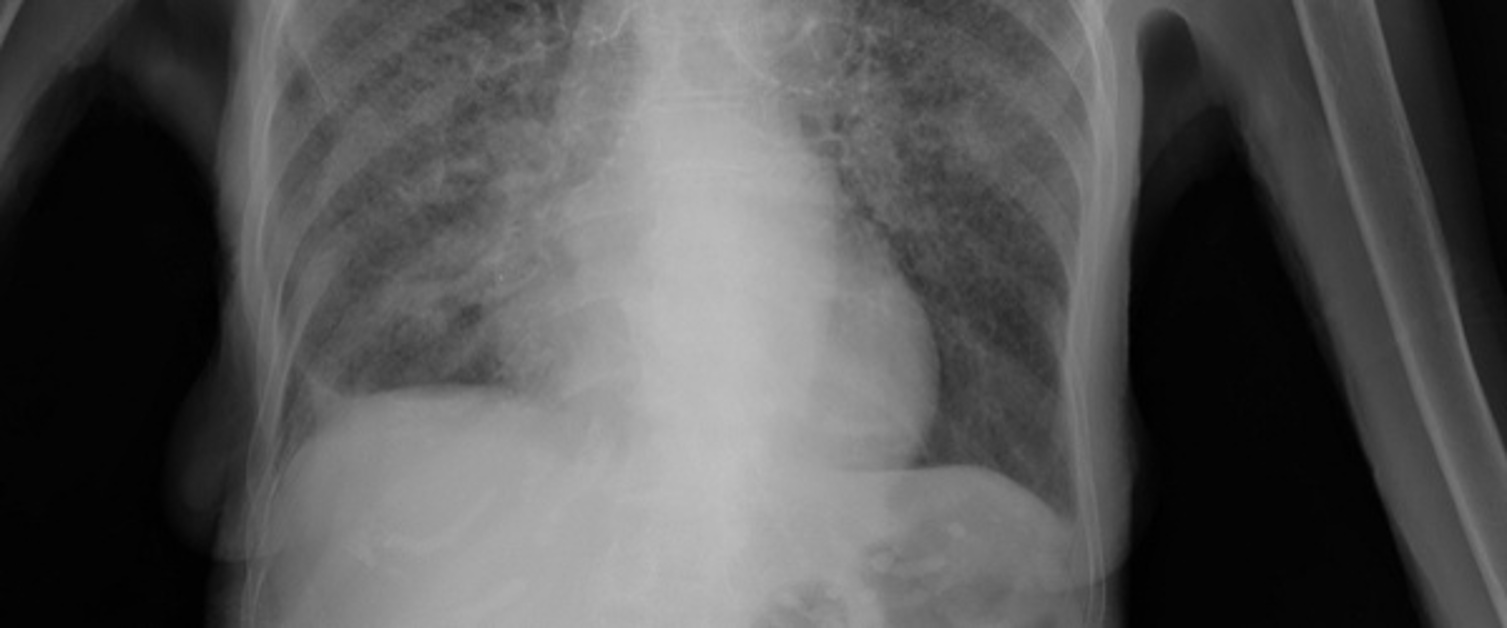

Mae twbercwlosis (TB) yn heintiad bacterol sy'n lledaenu trwy anadlu diferion bach o besychiadau a thisiadau gan rywun sydd wedi'i heintio â thwbercwlosis. Mae'n effeithio'n bennaf ar yr ysgyfaint ond gall effeithio ar rannau eraill o'r corff.